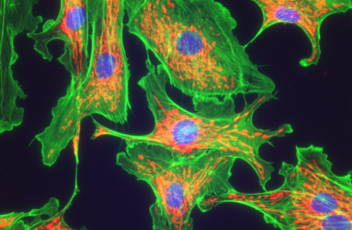

落射荧光

紧凑型落射荧光附件采用了专用的噪声终结机制,允许弱荧光标本与巨大的清晰度和亮度抓获。该过滤器的炮塔可以容纳四个过滤立方体,并改变它们很简单。高光学性能的物镜的落射荧光成像,包括CFI Plan Apochromat Lambda系列和CFI Plan Fluor系列,是可用的。

落射荧光附件和激发块